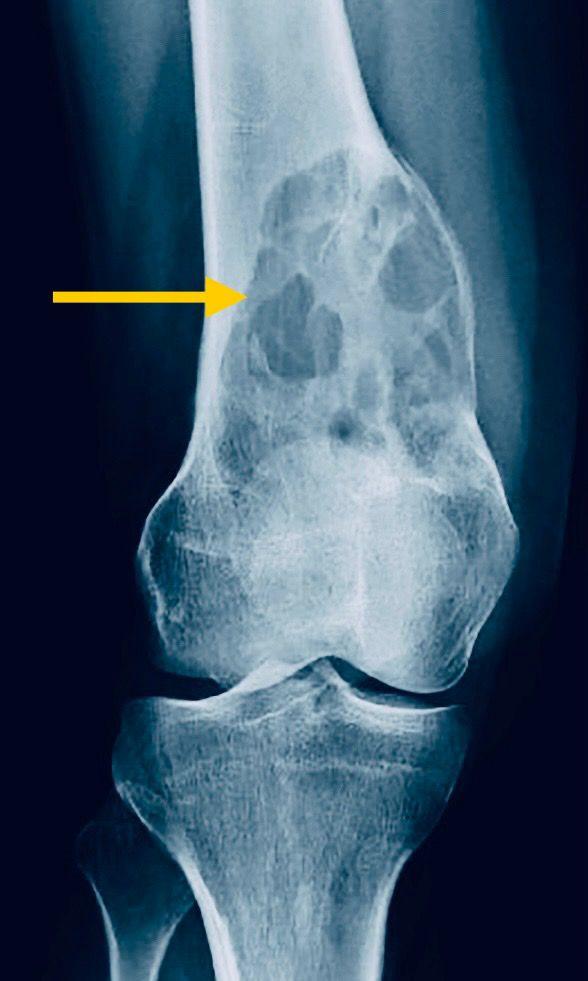

為要確診骨巨細胞瘤,患者須做影像檢查和組識化驗。X光檢查會顯示骨骼出現蝕骨性病變,而皮質骨亦有被侵蝕破壞的跡象。由於骨瘤生長速度快,因此骨骼未能形成硬化性邊界來阻擋它生長(情況就恍似美國的邊境圍牆,無法阻止非法移民湧入那樣)。然而,骨巨細胞瘤與原發性骨癌,在發病年齡、症狀與X光檢查上,都有不少相似地方,因此患者須進一步照電腦掃描和磁力共振,來為兩者區分。但醫生仍須抽取骨組織化驗,來確診並排除骨癌。